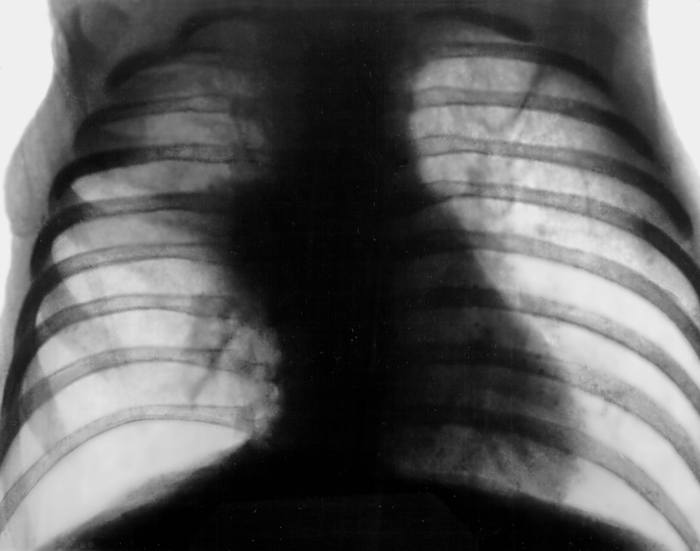

3. Бронхолегочная форма наблюдается при избыточной продукции густой слизи в респираторном тракте. Манифест заболевания часто связан с перенесенным ОРВИ. В результате повышенной плотности секрета наблюдается обструкция дыхательных путей. Нередко наблюдается вторичное инфицирование респираторного тракта. Тяжелые пневмонии, гнойно-обструктивные бронхиты имеют рецидивирующий характер, частота их возникновения достигается нескольких случаев в год. Вторичные изменения дыхательной системы проявляются эмфиземой, бронхоэктазами, пневмосклерозом, формированием легочного сердца. Вторичная инфекция чаще вызвана синегнойной палочкой, стафилококком, гемофильной палочкой или их ассоциациями. Обнаруженные микроорганизмы проявляют высокую чувствительность к распространенным антибиотикам. Наблюдается высокая летальность, обусловленная развитием дыхательной и сердечной недостаточности. На долю бронхолегочной формы отводят до 20% случае муковисцидоза.